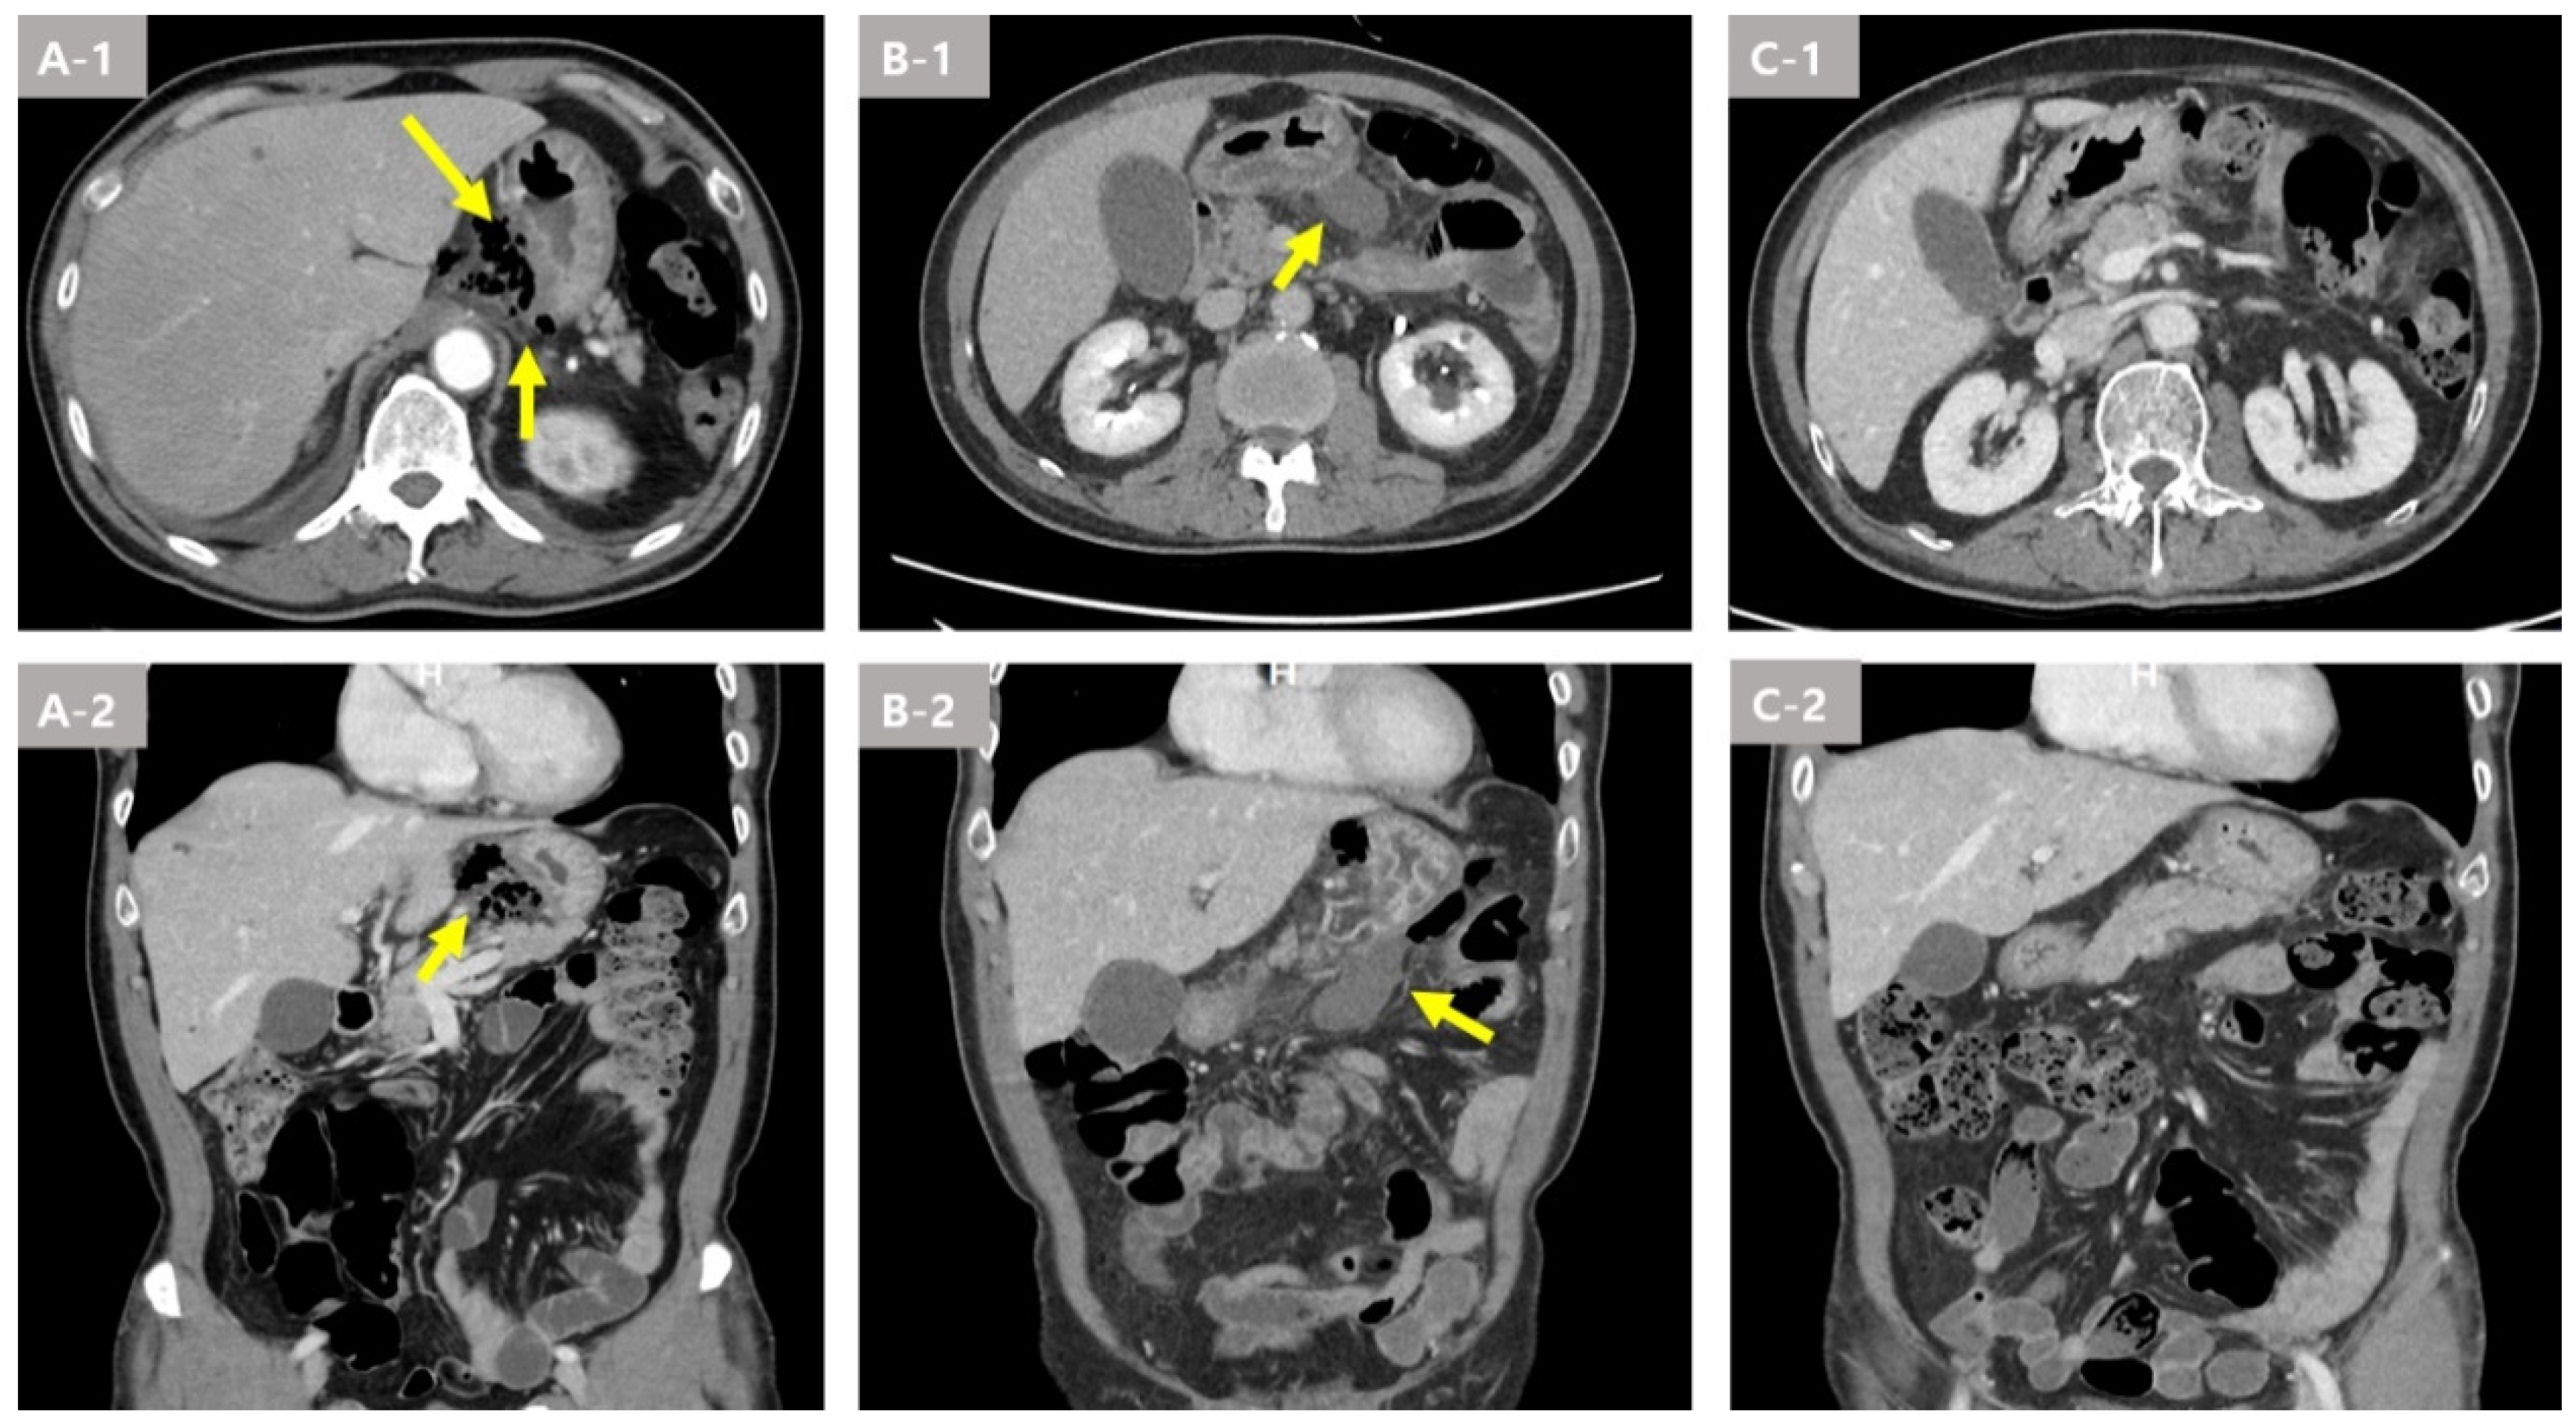

On day three of hospitalization, a chest and abdomen CT scan showed distal esophageal perforation with abscess and infectious fluid in the posterior mediastinum and lesser sac. The upper endoscopy showed a small mucosal opening that appeared to be punctured up to the muscle layer at the 40 cm from the UI (Figure 4A). Percutaneous abscess drainage (PCD) insertion was performed for fluid collection at the Lt. pleural space.

One week later, a chest CT scan showed an increased amount of fluid collection in the lesser sac and greater omentum (Figure 3(B-1,B-2)). On the follow up upper endoscopy, continuous drainage of whitish exudate at the perforation site was observed (Figure 4B). PCD insertion was performed for fluid collection at the Lt. aspect of the stomach and peritoneal space.

After two weeks of hospitalization, a chest CT scan showed decreased fluid collection in the lower paraesophageal area and remnant fluid collection in the lesser omentum and pelvic cavity (Figure 3(C-1,C-2)). On the follow up upper endoscopy, the previously observed orifice was not visible (Figure 4C). Esophagography was performed prior to feeding, and there was no leakage.

Figure 4. Endoscopic findings of the distal esophageal perforation with descending peritoneal abscess due to an esophageal fish bone foreign body in Case 2. (A) A mucosal small ulcer was observed with endoscopy. (B) Continuous drainage of whitish exudate at the perforation site was observed with endoscopy. (C) Disappearance of the mucosal ulcer with endoscopy.